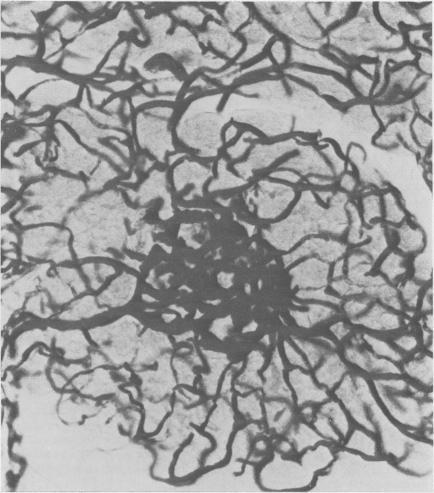

Henderson J R, Daniel P M, Fraser P A

Gut. 1981 Feb;22(2):158-67. doi: 10.1136/gut.22.2.158.